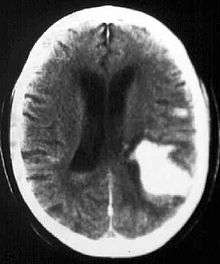

Computed tomography (CT scan): A CT scan may be normal if it is done soon after the onset of symptoms. A CT scan is the best test to look for bleeding in or around your brain. In some hospitals, a perfusion CT scan may be done to see where the blood is flowing and not flowing in your brain.

Magnetic resonance imaging (MRI scan): A special MRI technique (diffusion MRI) may show evidence of an ischemic stroke within minutes of symptom onset. In some hospitals, a perfusion MRI scan may be done to see where the blood is flowing and not flowing in your brain.